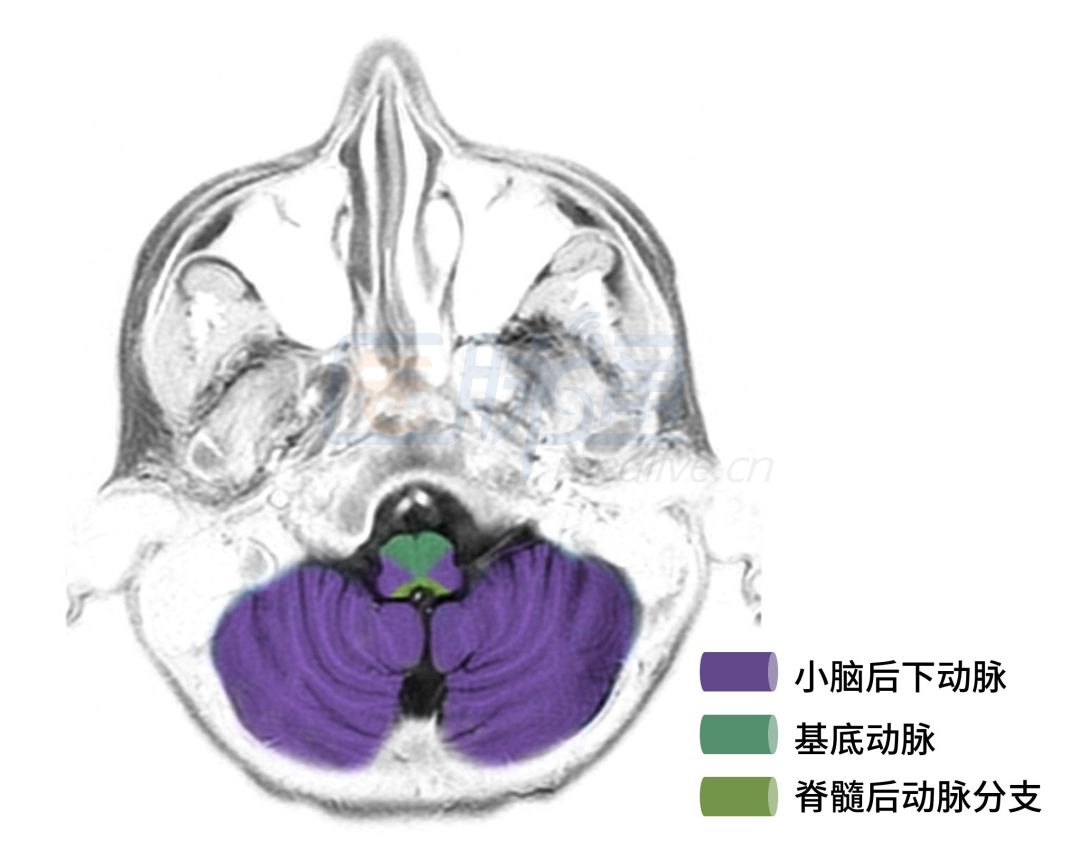

图5 小脑桥脑脚层面

图5显示的层面主要是小脑血管供应区域。

❖ 基底动脉:供应脑桥及小脑中脚,闭塞可引起桥脑中部基底综合症。

❖ 小脑前下动脉:供血小脑下部的前侧及脑桥下1/3,闭塞可引起桥脑基底外侧综合症。

❖ 小脑上动脉:供应中脑尾部和小脑后部,闭塞可引起桥脑被盖上部综合症。

❖ 小脑后下动脉:供应小脑蚓部,闭塞可引起躯干共济失调。